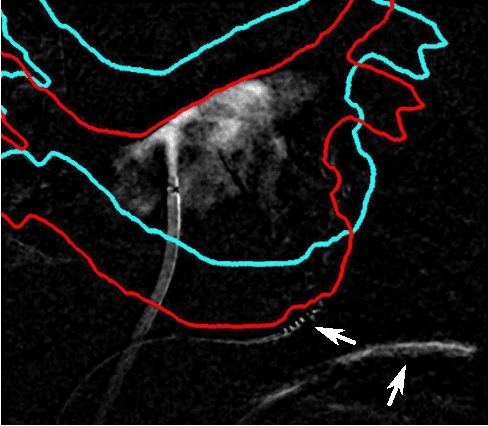

Abstract:For augmented fluoroscopy during cardiac catheter ablation procedures, a preoperatively acquired 3-D model of the left atrium of the patient can be registered to X-ray images. Therefore the 3D-model is matched with the contrast agent based appearance of the left atrium. Commonly, only small amounts of contrast agent (CA) are used to locate the left atrium. This is why we focus on robust registration methods that work also if the structure of interest is only partially contrasted. In particular, we propose two similarity measures for CA-based registration: The first similarity measure, explicit apparent edges, focuses on edges of the patient anatomy made visible by contrast agent and can be computed quickly on the GPU. The second novel similarity measure computes a contrast agent distribution estimate (CADE) inside the 3-D model and rates its consistency with the CA seen in biplane fluoroscopic images. As the CADE computation involves a reconstruction of CA in 3-D using the CA within the fluoroscopic images, it is slower. Using a combination of both methods, our evaluation on 11 well-contrasted clinical datasets yielded an error of 7.9+/-6.3 mm over all frames. For 10 datasets with little CA, we obtained an error of 8.8+/-6.7 mm. Our new methods outperform a registration based on the projected shadow significantly (p<0.05).